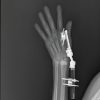

A 50-year-old woman complained of pain in her right wrist for 2 years. The pain was dull aching and aggravated on lifting objects with her right hand. She had a history of falls on her outstretched right hand 4 years earlier. She had no pain in other joints. She had no other pre-existing medical conditions and was right-hand dominant. On examination, tenderness was present over the dorsal aspect of the radial half of the wrist. Range of movements of the wrist was limited with palmar flexion of 50°, dorsiflexion of 40°, ulnar deviation of 30°, and radial deviation of only 10°. Watson’s scaphoid shift test was positive. Her grip strength was found to be 8 kg less than the contralateral side. Her blood parameters including rheumatoid profile were found to be within normal limits. Radiographs of the wrist revealed scapholunate diastasis, arthritis of radio-scaphoid joint (Fig. 1a), and dorsal intercalated segment instability (DISI) (Fig. 1b).

On further analysis of the radiographs, radial styloid beaking, and migration of capitate proximally into the space created by the scapholunate dissociation were also noted (Fig. 2a). Radiolunate joint space appeared normal. The scapholunate diastasis (Terry Thomas Sign) was measured and found to be 6.25 mm (Fig. 2b), which is normally supposed to be <3 mm. The lunate wound was found to be dorsally tilted about 30° from neutral (Fig. 2c), indicating the DISI deformity. The scapholunate angle was measured to be 100° (Fig. 2d), while it is normally expected to be between 30° and 60°. She was therefore diagnosed with SLAC. As per the Watson and Ballet classification of SLAC, it was classified as grade II, the radio-scaphoid joint was involved, but the capitolunate joint appeared normal [8]. She underwent conservative management with non-steroidal anti-inflammatory drugs for 2 months but only had partial relief of symptoms. She was then given a local corticosteroid injection and the wrist was splinted for 1 month. She had satisfactory pain relief allowing her to return to her normal activities. The range of movements of the wrist improved to palmar flexion of 70°, dorsiflexion of 60°, ulnar deviation of 40°, and radial deviation of 15°. Correspondingly her grip strength also improved and was found to be only 5 kg less than the contralateral side when measured 1 month following the corticosteroid injection. This was sufficient for her to be able to carry on her routine daily activities and vocation without pain, and hence, no surgical intervention was performed during the 3 years of follow-up.